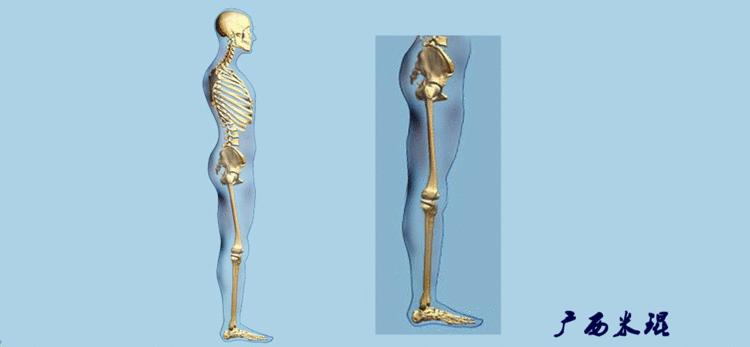

机械轴要分前后位及侧位,站立前后位(也就是冠状面)股骨头中心与踝关节中心的连线通过膝关节中心,这是下肢的机械轴线,也就是下肢力线,常说Mikulicz线。冠状面的力线评估在临床工作中最常用、最基础、最重要。

站立侧位(矢状面)股骨头中心与踝关节中心的连线也通过膝关节中心,这也是下肢的机械轴线,这也是下肢力线。

矢状面的下肢力线常常被医生忽视,其实它的改变也是膝关节疼痛的常见原因。

也就是下肢的负重轴,它是身体的纵轴线,与地面垂直,由于双髋比双踝的距离宽,所以垂直轴与下肢力线(机械轴)存在3°的外翻。

开始接触时可能我们对这些轴有点混乱,通过下面的这张图片就能清楚的了解下肢几个轴之间的关系。